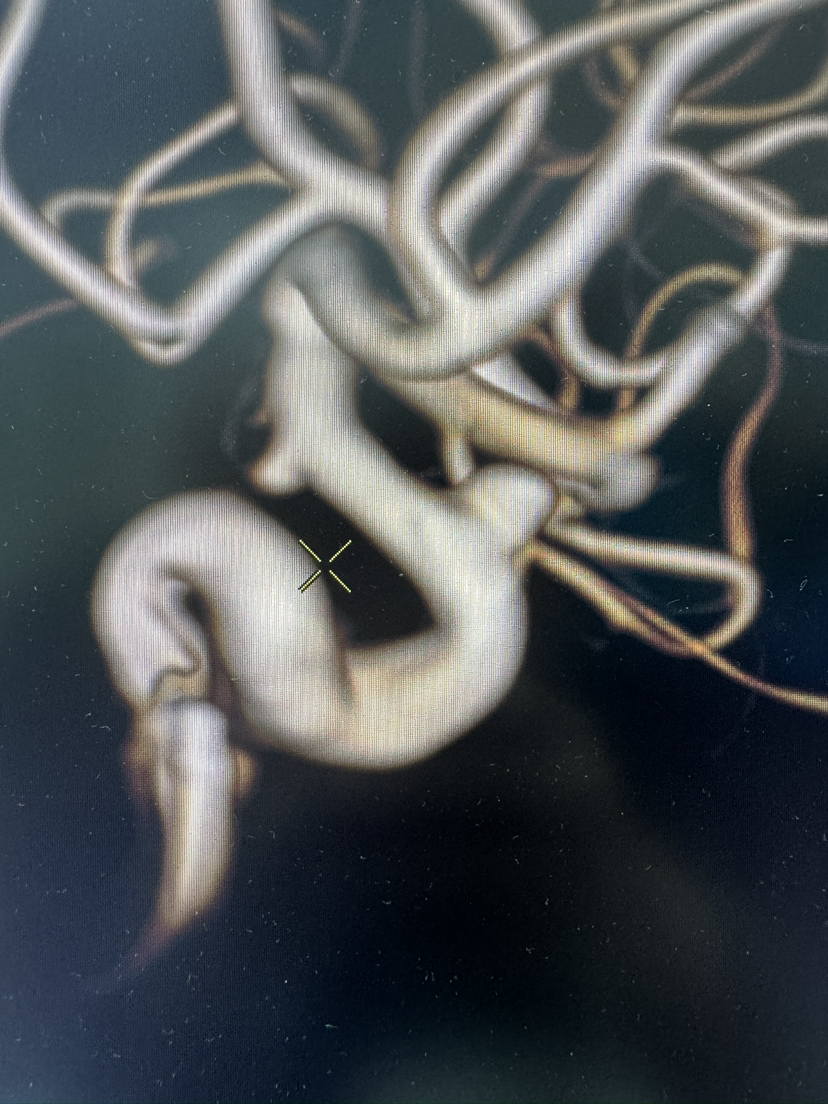

FRED血流导向密网支架栓塞眼动脉动脉瘤

#FRED®21 & FRED®27 血流导向密网支架

密网支架

动脉瘤

眼动脉